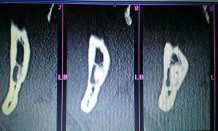

Voici le scanner d'un patient chez qui l'extraction des dents 47 et 48 est indiquée. Etant donné le positionnement de ces dents par rapport au nerf, j'aurais aimé avoir vos différents points de vue quant à la meilleure solution thérapeutique à adopter.

Il y a un risque de compression legere du V3 sans plus. Bien separer les racines de 48 et voir avec 47, si elle sort facilement sinon separer aussi apres lambeau 47-48 et fraisage osseux vestibulaire pour facilier une extraction dans sens linguo vestibulaire.

Pas d'indication de coronectomie pour moi.

+1 pour le risque de paresthésies transitoires. pas de risque de lésion irréversible si chirurgie bien menée.